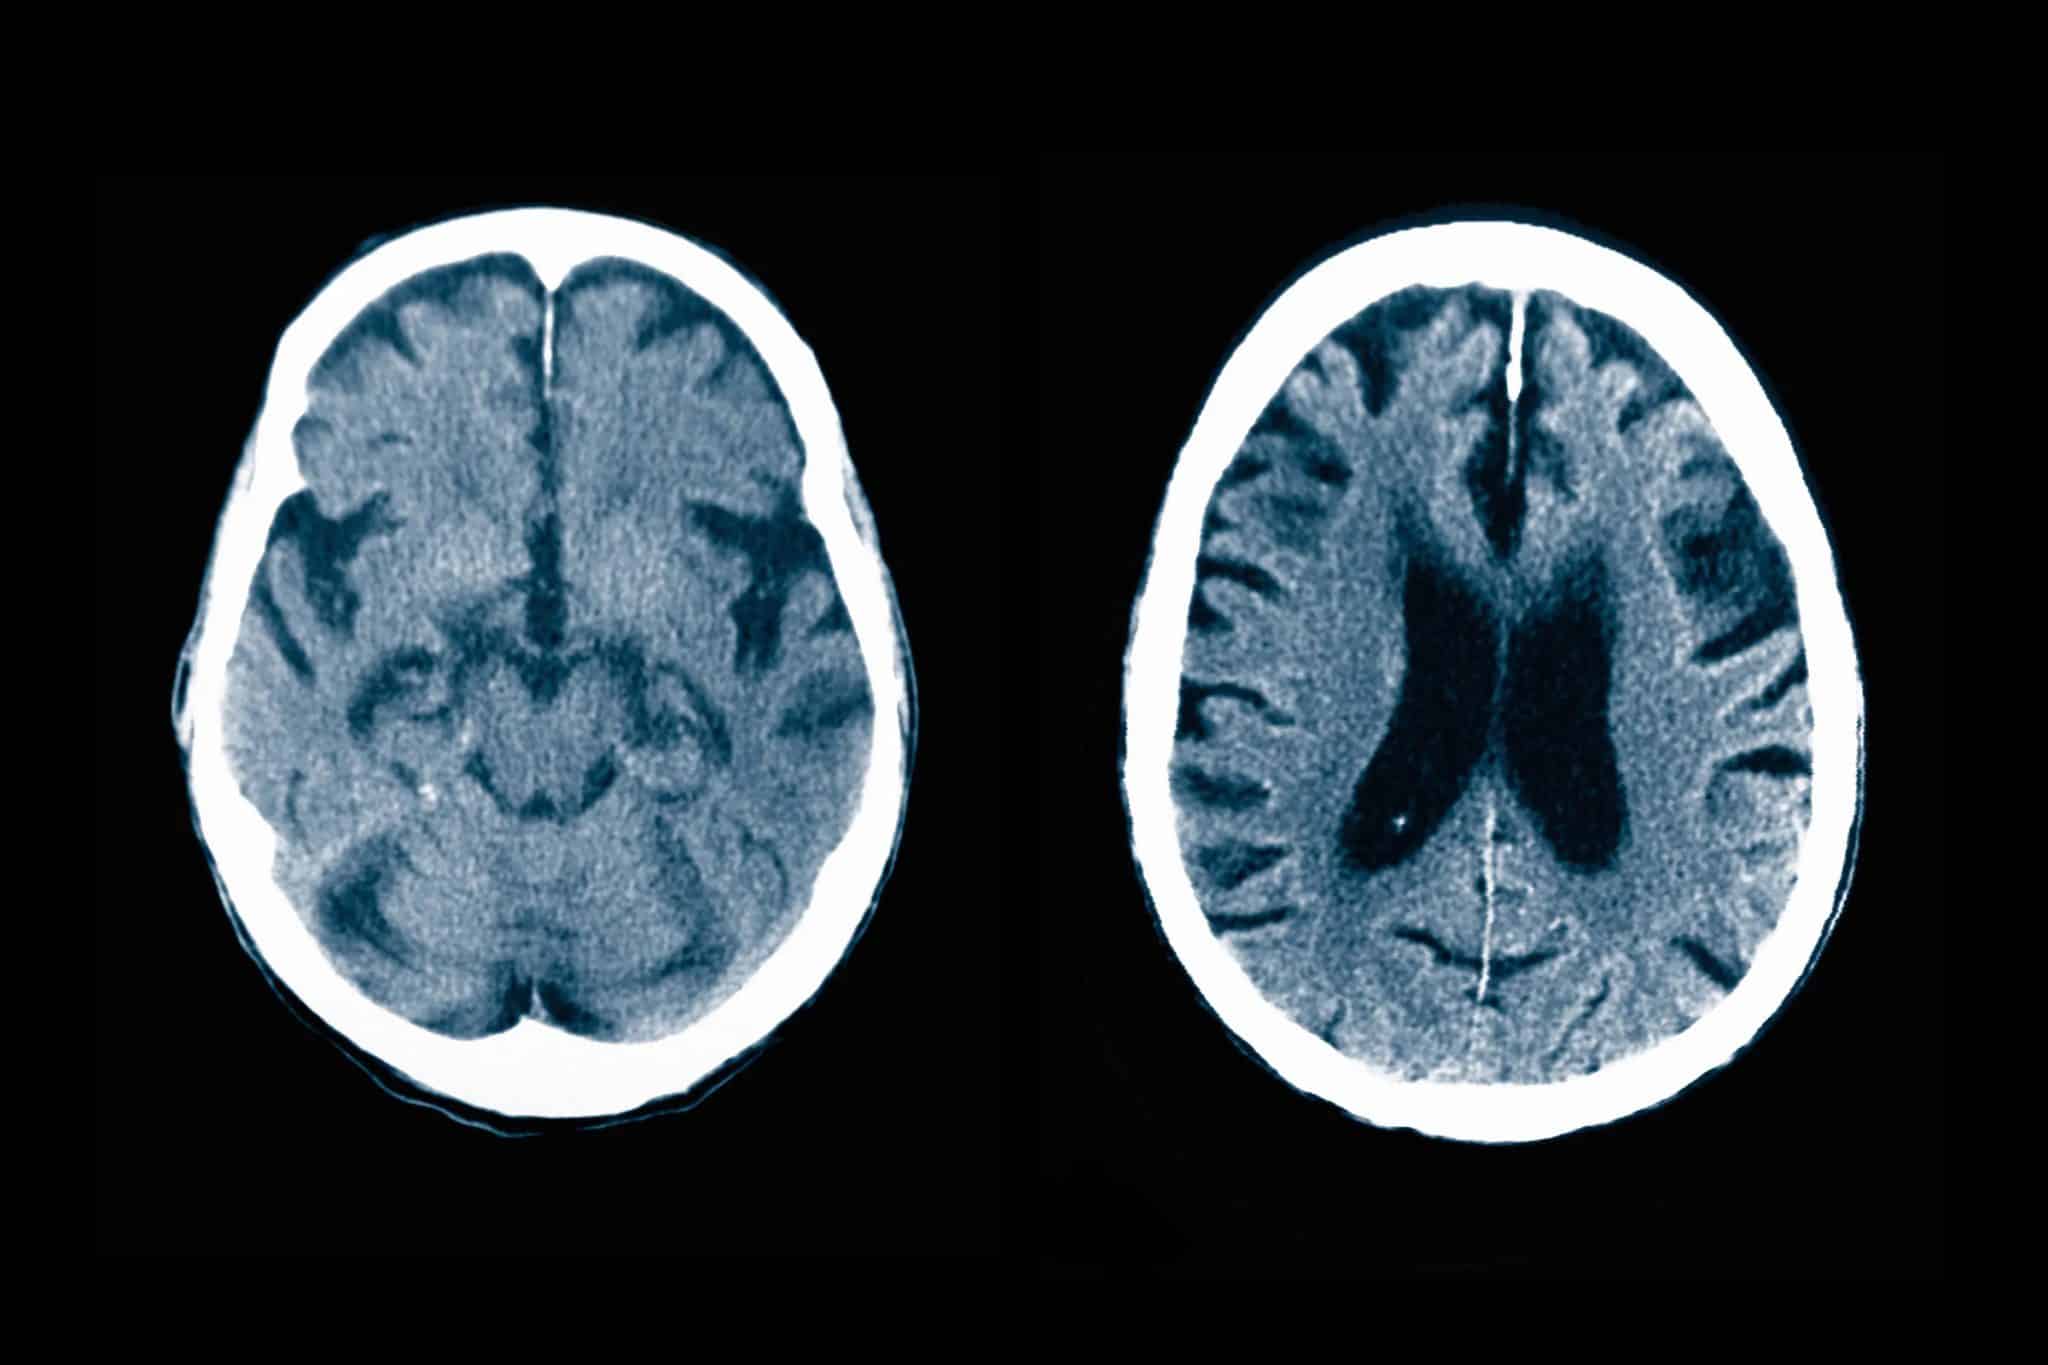

Диабет повлиял на работу мозга, подобно ранним стадиям болезни Альцгеймера   Медицина

Из прошлых исследований известно, что пациенты с диабетом второго типа более склонны к психиатрическим и нейродегенеративным расстройствам, но природа этой связи изучена недостаточно. Американские ученые недавно выяснили, что диабет способен …

МРТ-снимки головного мозга с признаками атрофии  / © Callista images/Getty images

Диабет второго типа и амилоидные белки ускорили атрофию мозга   Медицина

Международная команда ученых из Университета Джонса Хопкинса (США) провела уникальное исследование, наблюдая за 185 людьми на протяжении 20 лет. В результате команда определила ряд факторов, ускоряющих отмирание клеток головного мозга. …